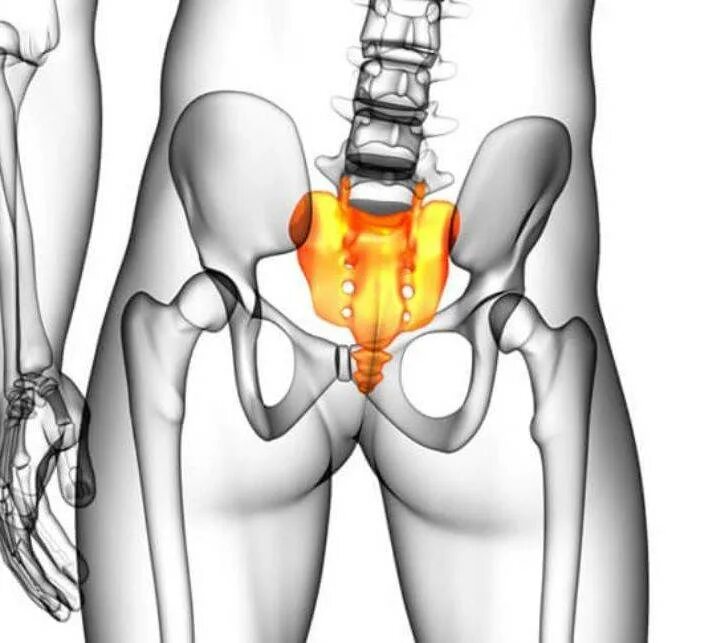

Кости таза анатомия крестец. тазовая поверхность крестца анатомия. крестец и копчик анатомия человека. крестцы таз человека.

Строение крестца. боковая масса крестца анатомия. крестец строение анатомия. где находится крестцовая кость.